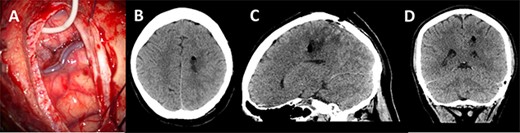

Post-operative imaging; (A) post-decannulation brain surface after transsulcal approach; (B–D) axial, sagittal and coronal CT images showing collapse of the surgical tract and no overt complications.

A post-operative CT head was performed within 24 h of surgery documenting collapse of the surgical tract (Fig. 5). The patient did not have any post-operative deficit and was discharged home. Histopathology confirmed a Glioblastoma Multiforme.